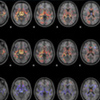

Emotion and the brain: Mapping the missing link

Derek Mitchell, PhD, is bridging the gap between our understanding of the mind and its relationship to the physical brain. He studies the neuroanatomy underlying the experience and control of emotions, such as fear, anxiety and anger.